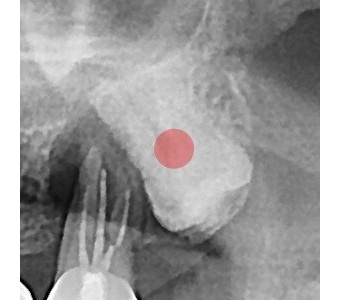

결과로 증명합니다.

국제모아치과의

실제 임상 증례